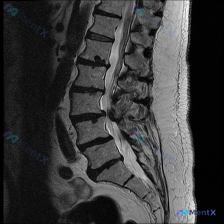

整理了一份影像读片的病例材料,先抛出来大家一起讨论: - 影像来源:腰椎MRI(T2序列,矢状位) - 核心影像表现: 1. L2/L3、L3/L4、L4/L5椎间盘T2低信号(黑盘征),L5/S1信号也有减低;L4/L5、L5/S1椎间隙略窄,伴椎间盘向后弥漫膨出,硬膜囊前缘受压、变形,相应节段椎...

整理到一份腰椎MRI T2加权矢状位的影像分析资料,用户一开始关注的是「脊柱侧弯(Scoliosis)」,但仔细读下来,里面还有几个更值得讨论的影像表现: - 多节段(L2/3到L5/S1)椎间盘T2信号减低,「黑盘征」 - L4/5、L5/S1椎间盘突出,压迫硬膜囊,局部椎管狭窄 - L4、L5邻...